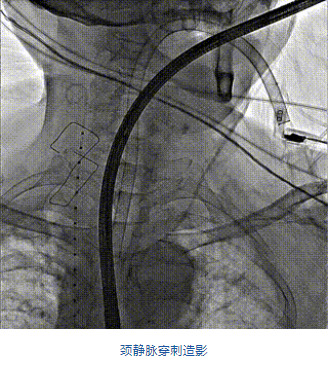

團隊前期經過多次討論,制定了周密的手術策略和預案。由于患者已是近九旬的超高齡老人,傳統外科開胸手術風險極高,純介入經血管三尖瓣替換能夠明顯減少創傷。術中陳茂及馮沅教授結合體表定位在造影指示下精準穿刺右側頸靜脈并預置兩把血管縫合器。成功建立經皮血管入路后在食道超聲和DSA的引導下順利完成人工瓣膜植入,術后超聲和造影顯示人工三尖瓣同軸性良好,瓣架固定牢靠,無反流和瓣周漏,平均跨瓣壓差降為1mmHg。術畢收緊預置的血管縫合器縫線完成止血,縫合效果滿意,在手術室即刻拔除氣管插管。